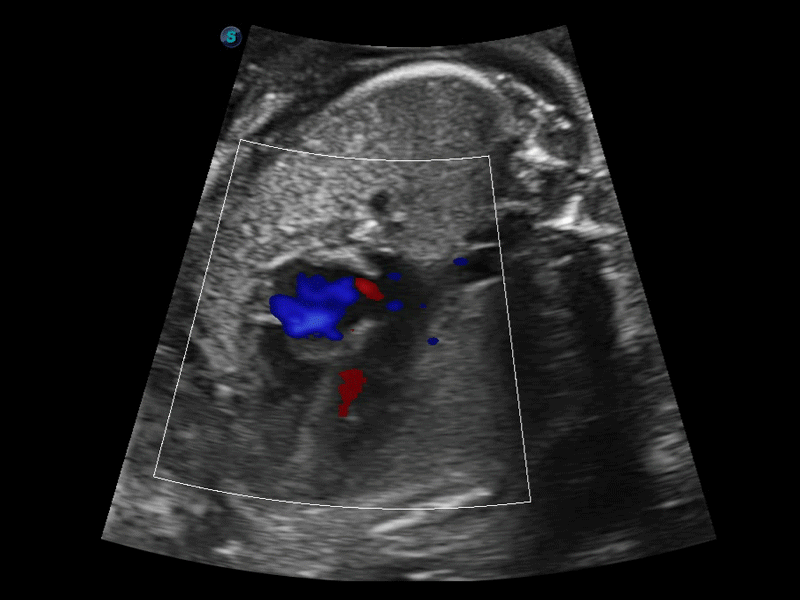

SR Flow高分辨率血流成像

高分辨率血流成像技术提高了对低速血流信号的检测能力。在提高空间分辨率的同时,也克服了血流外溢现象,为用户提供更加真实的血流动力学信息。

临床图像